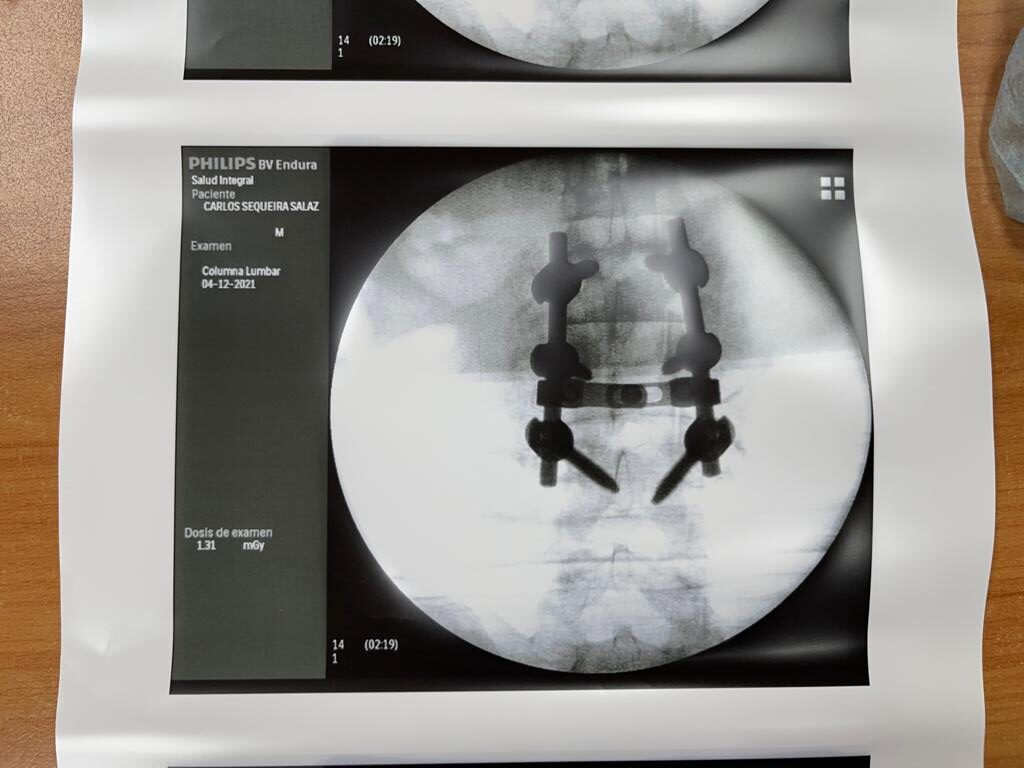

4. Fusión Vertebral (Lumbosacra o Cervical)

¿Qué es?

Cirugía que une dos o más vértebras para estabilizar la columna y aliviar el dolor.

Fusión Vertebral (Cervical o Lumbosacra)

Es un procedimiento quirúrgico que busca estabilizar la columna vertebral uniendo de forma permanente dos o más vértebras. Se utilizan tornillos, barras y, en ocasiones, una caja intersomática con injerto óseo, para que las vértebras se fusionen en una sola unidad sólida.